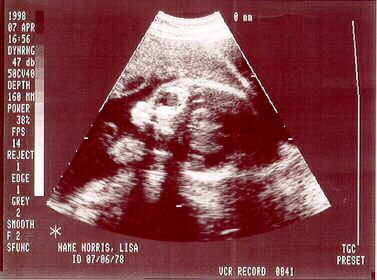

Sonogram Pictures

my face

my feet